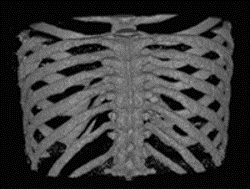

在应用案例中,经过对应用该算法的深度学习Caffe框架的数据训练,其成功实现了从胸部CT影像中自动化识别和提取胸骨组织。同时,在对被识别和提取的骨组织影像进行排序和整理的此基础上,该研究优化了体绘制算法并利用OpenGL渲染技术实现了胸骨组织的几何自动化建模。

从而,算法和程序实现了从胸部CT影像的导入直到相关骨组织的识别、提取和几何重构建模的所有工作自动化完成。基于人工智能深度学习的高识别精度,上述所有识别和建模工作均可一次性精准地自动化完成,无需额外的人工修正。